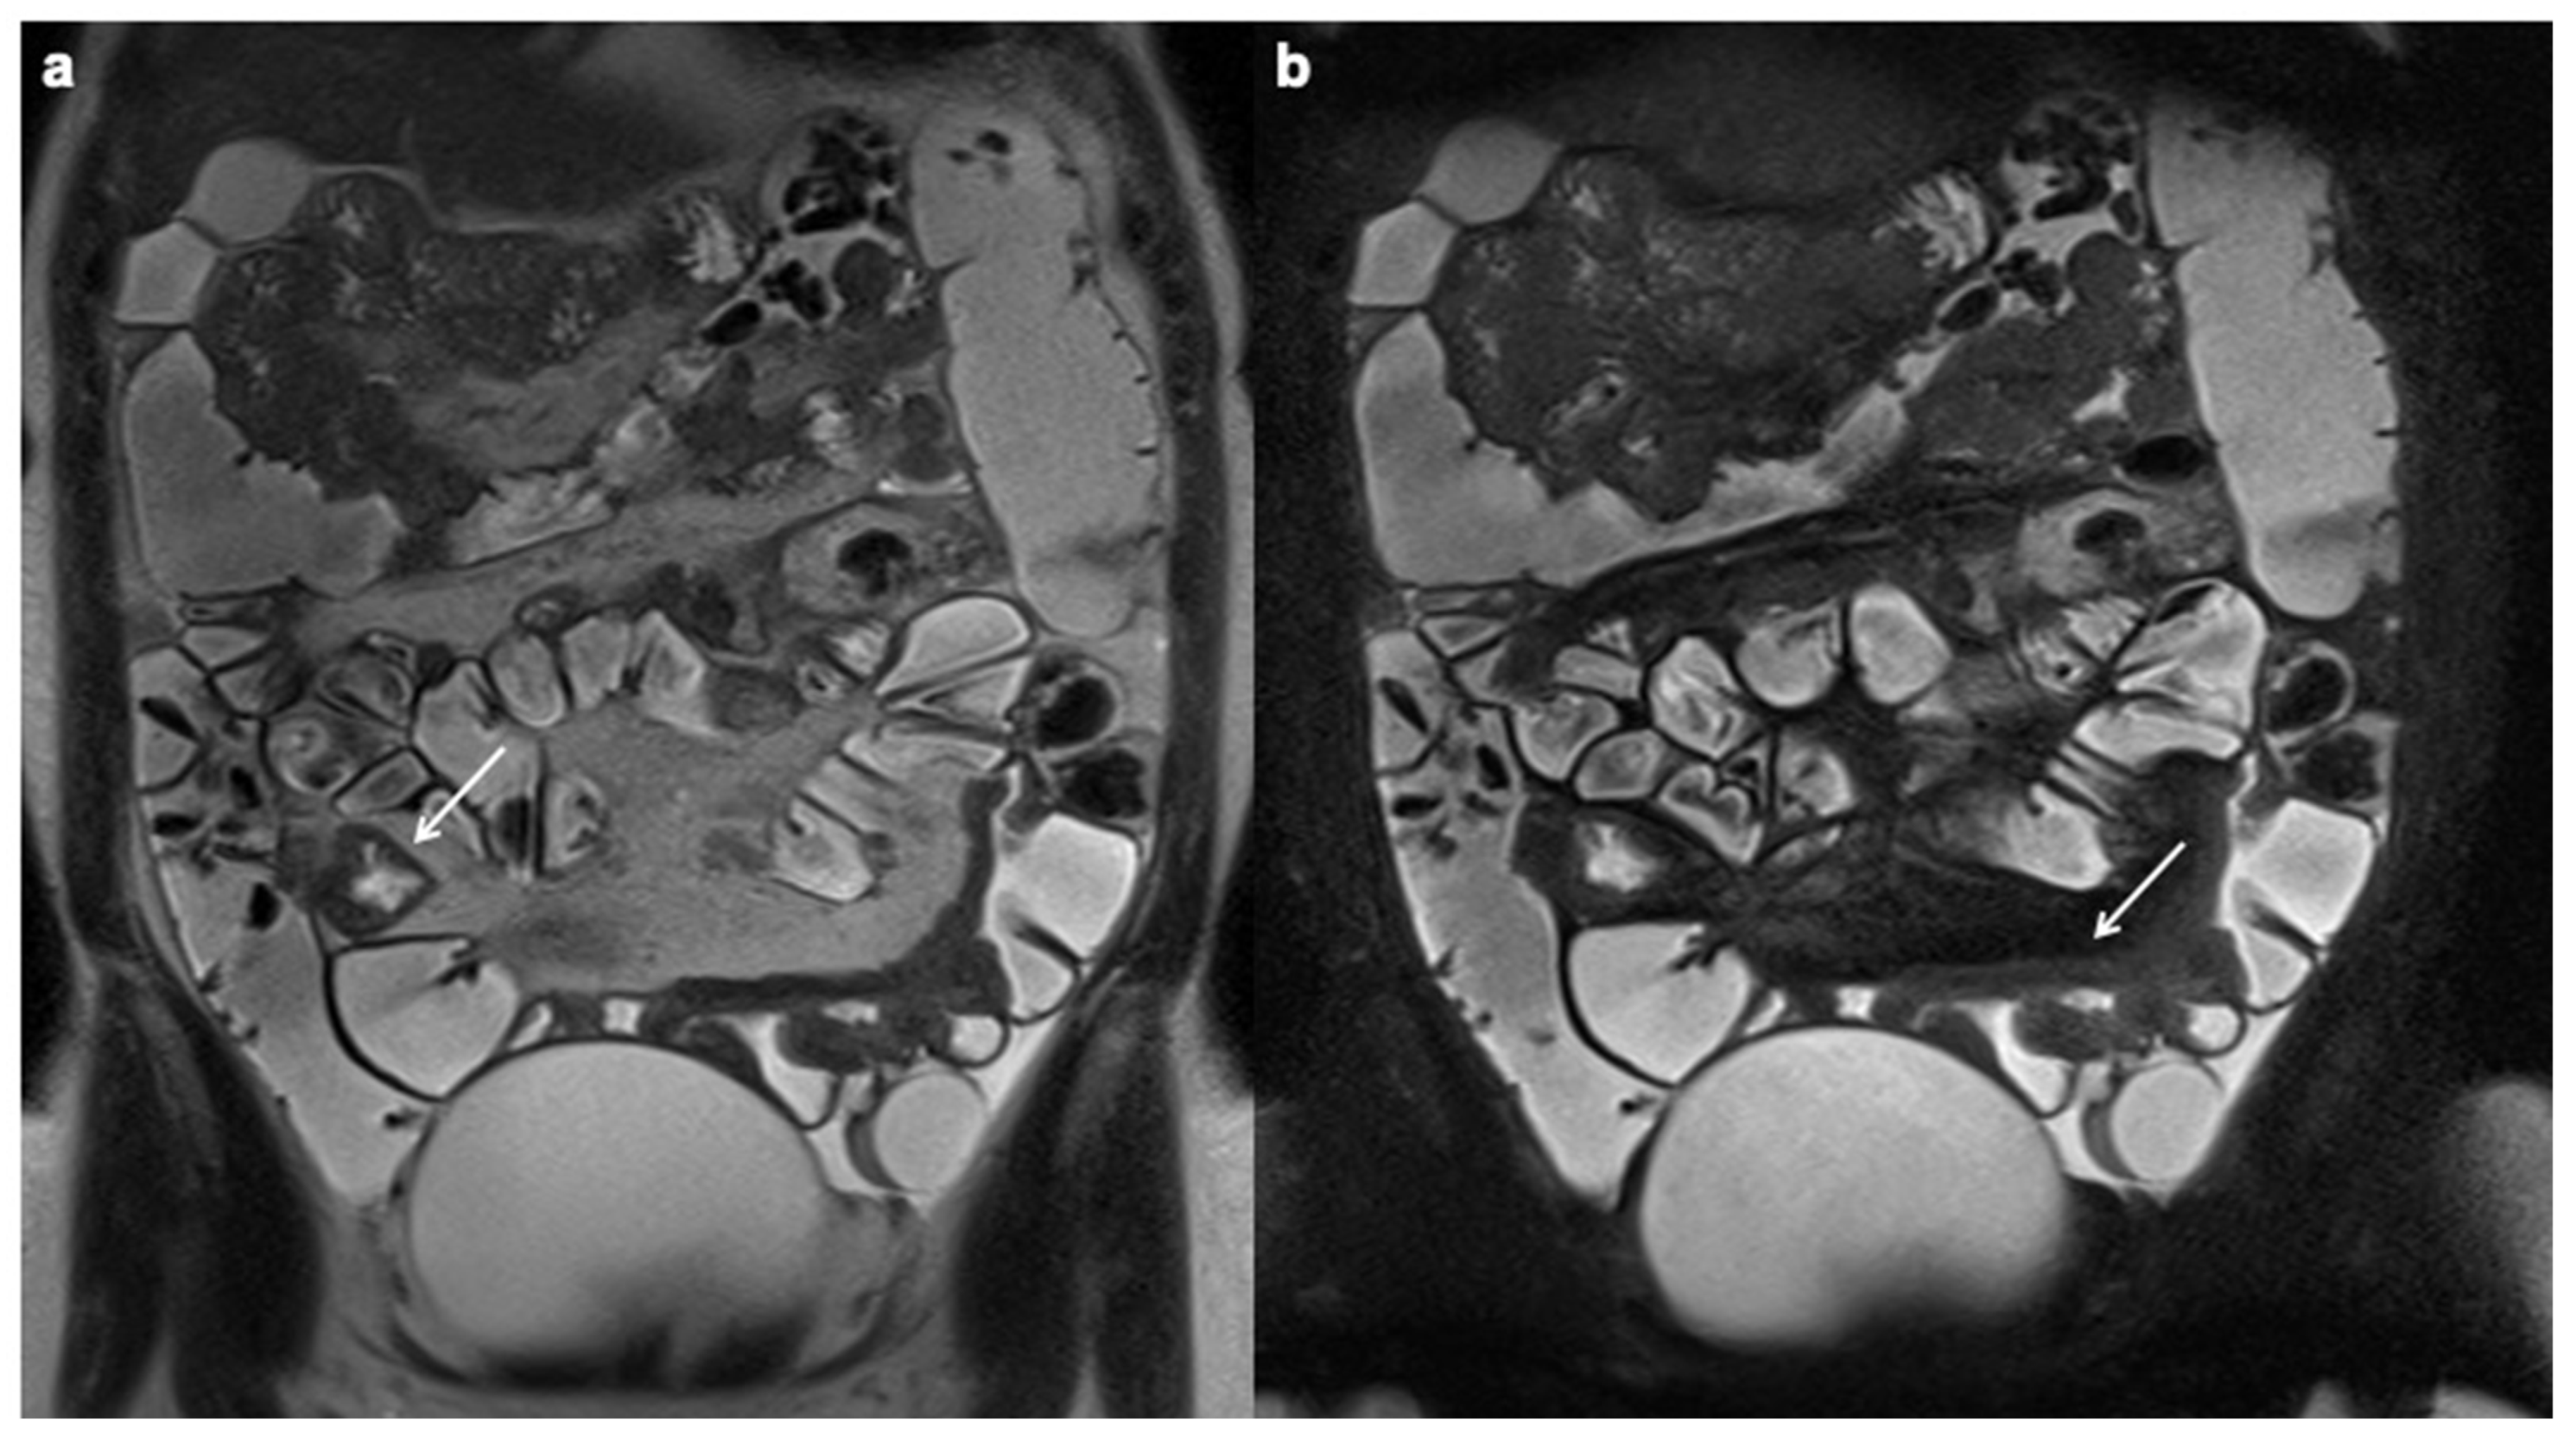

10. Imaging Findings Associated with Active CD Inflammation

- Church, P.C.; Turner, D.; Feldman, B.M.; Walters, T.D.; Greer, M.-L.; Amitai, M.M.; Griffiths, A.M.; the ImageKids study group. Systematic review with meta-analysis: Magnetic resonance enterography signs for the detection of inflammation and intestinal damage in Crohn’s disease. Aliment. Pharmacol. Ther. 2014, 41, 153–166. [Google Scholar] [CrossRef]

- Tolan, D.J.M.; Greenhalgh, R.; Zealley, I.A.; Halligan, S.; Taylor, S.A. MR Enterographic Manifestations of Small Bowel Crohn Disease. RadioGraphics 2010, 30, 367–384. [Google Scholar] [CrossRef] [Green Version]

- Sinha, R.; Verma, R.; Verma, S.; Rajesh, A. MR Enterography of Crohn Disease: Part 2, Imaging and Pathologic Findings. Am. J. Roentgenol. 2011, 197, 80–85. [Google Scholar] [CrossRef] [Green Version]

- Punwani, S.; Rodriguez-Justo, M.; Bainbridge, A.; Greenhalgh, R.; De Vita, E.; Bloom, S.; Cohen, R.; Windsor, A.; Obichere, A.; Hansmann, A.; et al. Mural Inflammation in Crohn Disease: Location-Matched Histologic Validation of MR Imaging Features. Radiology 2009, 252, 712–720. [Google Scholar] [CrossRef]

- Choi, D.; Lee, S.J.; Cho, Y.A.; Lim, H.K.; Kim, S.H.; Lee, W.J.; Lim, J.H.; Park, H.; Lee, Y.R. Bowel Wall Thickening in Patients with Crohn’s Disease: CT Patterns and Correlation with Inflammatory Activity. Clin. Radiol. 2003, 58, 68–74. [Google Scholar] [CrossRef] [PubMed]

- Steward, M.J.; Punwani, S.; Proctor, I.; Adjei-Gyamfi, Y.; Chatterjee, F.; Bloom, S.; Novelli, M.; Halligan, S.; Rodriguez-Justo, M.; Taylor, S. Non-perforating small bowel Crohn’s disease assessed by MRI enterography: Derivation and histopathological validation of an MR-based activity index. Eur. J. Radiol. 2012, 81, 2080–2088. [Google Scholar] [CrossRef]

- Rimola, J.; Ordás, I.; Rodriguez, S. Magnetic resonance imaging for evaluation of Crohn’s disease: Validation of parameters of severity and quantitative index of activity. Inflamm. Bowel Dis. 2011, 17, 1759–1768. [Google Scholar] [CrossRef]

- Rimola, J.; Rodriguez, S.; Garcia-Bosch, O.; Ordas, I.; Ayala, E.; Aceituno, M.; Pellise, M.; Ayuso, C.; Ricart, E.; Donoso, L.; et al. Magnetic resonance for assessment of disease activity and severity in ileocolonic Crohn’s disease. Gut 2009, 58, 1113–1120. [Google Scholar] [CrossRef] [PubMed] [Green Version]